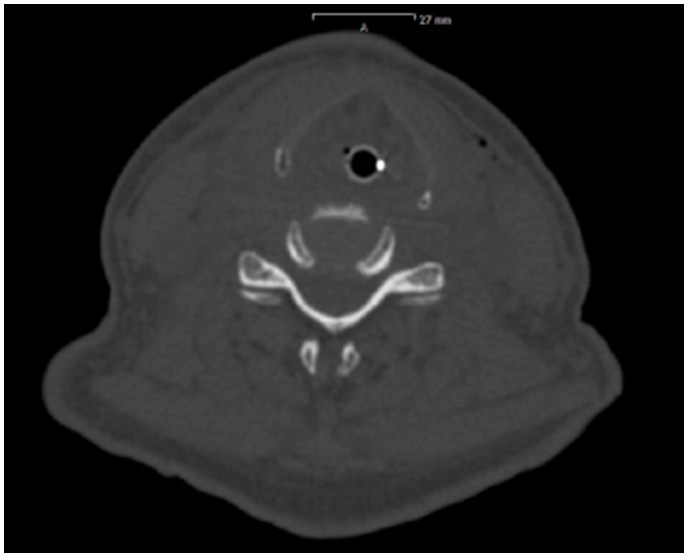

Figure 3: Postoperative CT-scan: Larynx, hypopharynx and parts of the oropharynx heavily edematous. Lumen of trachea in the neck area just kept braced by the tubus.

figure 3